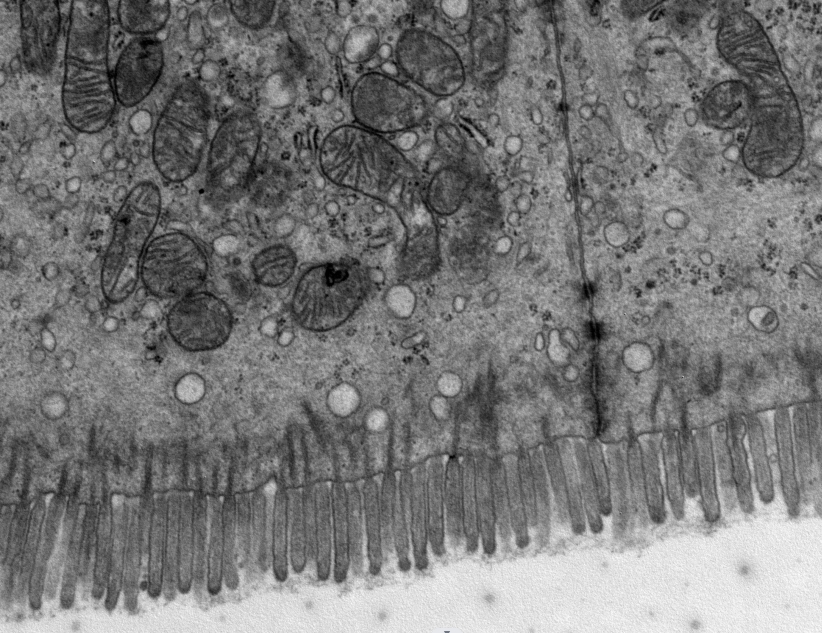

透射電鏡(TEM),全稱透射電子顯微鏡,是把經(jīng)加速和聚集的電子束投射到超薄切片的樣品上(通常70-90nm),電子與樣品中的原子碰撞而改變方向,從而產(chǎn)生立體角散射。散射角的大小與樣品的密度、厚度相關(guān),因此可以形成明暗不同的影像,影像將在放大、聚焦后在成像器件上顯示出來。是一種高分辨率(0.1nm-0.2nm)、高放大倍數(shù)(0.2K-600K)的顯微鏡。是觀察和研究物質(zhì)超微結(jié)構(gòu)的強(qiáng)有力工具。透射電鏡在細(xì)胞生物學(xué)、組織學(xué)、病毒學(xué)、病理學(xué)、分子生物學(xué)、材料科學(xué)等諸多領(lǐng)域具有廣泛應(yīng)用??梢杂^測動(dòng)物植物細(xì)胞超微結(jié)構(gòu),如線粒體、內(nèi)質(zhì)網(wǎng)、高爾基體、溶酶體、葉綠體、液泡、細(xì)胞內(nèi)生細(xì)菌等結(jié)構(gòu)及病理變化??梢杂^測病毒顆粒、外泌體、病原微生物、各類細(xì)菌真菌、納米材料及納米顆粒、晶體結(jié)構(gòu)。